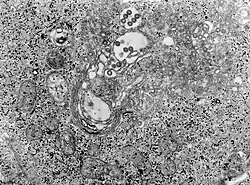

Rifttalfieber-Viren im Elektronenmikroskop (Quelle: CDC) | ||||||||||||||||||||

Die Erreger des Rifttalfiebers sind Viren der Spezies Rift Valley fever phlebovirus (RVFV, Rifttal-Fieber-Virus) aus der Gattung Phlebovirus der Familie Phenuiviridae in der Ordnung Bunyavirales. Es handelt sich um Einzelstrang-RNA-Viren. Ihr Genom ist segmentiert in drei Teile (tripartit). Es wird zwar gewöhnlich als mit negativer Polarität klassifiziert, tatsächlich sind die Verhältnisse aber komplizierter: Das L- und M-Segment haben beide negative Polarität (englisch negative-sense), aber das S-Segment (und damit das gesamte Genom) ist ambisense.[5] Die drei Genomsegmente kodieren für 6 Hauptproteine:[5]

Wie bei allen Bunyaviren haben die Virusteilchen (Virionen) von RVFV eine äußere Lipidhülle (mit den beiden Glycoproteinen – G(N) und G(C)). Diese werden für den Eintritt in die Wirtszelle benötigt, denn sie verschmelzen die Virushülle mit deren endosomaler Membran und bringen so das virale Genom in die Wirtszelle ein.